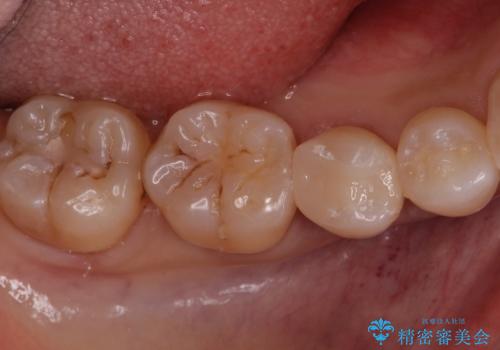

[ 歯並びと虫歯治療 ] 矯正治療とセラミック治療の包括治療

![[ 歯並びと虫歯治療 ] 矯正治療とセラミック治療の包括治療の症例 治療前](https://seimitsushinbi.jp/wp/wp-content/uploads/2023/12/IMG_1093-500x350.jpg?v=1703058764)